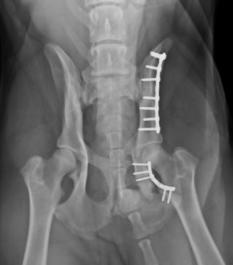

Boiteries et Fractures : Les    boiteries    :     qu’elles     soient    spontanées,    sur    un    membre    ou    sur    tout    le    train    arrière, intermittentes   (importantes   le   matin,   plus   discrètes   après   de   l’exercice),   ou   progressives   avec l’âge, il n’y a pas deux boiteries équivalentes. Certaines   demandent   un   traitement   immédiat,   précédé   de   clichés   radio,   d’autres   se   traitent   à l’aide   d’anti-inflammatoire   pour   soulager   la   douleur   comme   souvent   chez   le   chien   et   d’autres encore   comme   chez   le   chat   nécessite   des   antibiotiques   tant   la   suspicion   de   morsure   par   un congénère est importante . Une   fracture   ouverte   :   une   chute   ?   Un   accident   sur   la   route   ?   Toujours   est   il   que   votre   animal   ne pose   plus   un   membre,   qu’il   a   une   vilaine   plaie   qui   peut   faire   apparaître   les   tissus   profonds,   peut- être des os brisés. C’est une urgence à gérer au plus vite. Nettoyez   les   bords   de   la   plaie   avec   un   savon   médical   (bétadine   moussante,   ou   autre),   et   ne donnez   rien   comme   médicament   qui   pourrait   déranger   l’anesthésie   ou   les   conditions   opératoires pour votre vétérinaire. Gérer   l’urgence   d’abord   !   :    La   majorité   des   propriétaires   pensent   que   la   première   chose   à   faire est   une   radiographie   du   membre   fracturé,   hors,   c’est   à   priori   la   chose   que   nous   ferons   en   dernier après   avoir   stabilisé   l’animal.   Les   radios   des   membres   sont   souvent   effectuées   le   lendemain   de l’hospitalisation   après   avoir   fait   une   bonne   gestion   de   la   douleur   (morphine,   etc.)   et   après   avoir traiter un éventuel état de choc.

boiterie chat chien bagarre chirurgie orthopedique chat chien radio fracture chien chat